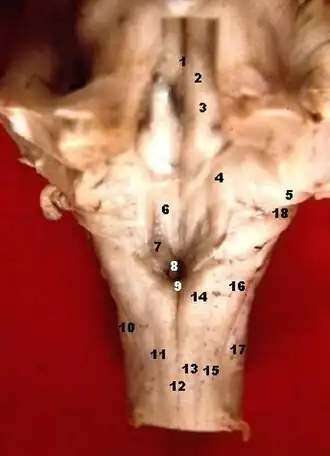

Human caudal brainstem posterior view (Colliculus facialis is #3) | |

The facial colliculus is an elevated area located in the pontine tegmentum (dorsal pons), within the floor of the fourth ventricle (i.e. the rhomboid fossa). It is formed by fibres from the facial motor nucleus looping over the abducens nucleus. The facial colliculus is an essential landmark of the rhomboid fossa.[1]

The facial colliculus occurs within the rhomboid fossa (i.e. the floor of the fourth ventricle) where it is placed lateral to its (midline) median sulcus.[1]

The facial colliculus is formed by brachial motor nerve fibres of the facial nerve (CN VII) looping over the (ipsilateral) abducens nucleus, forming a bump upon the surface.[1]